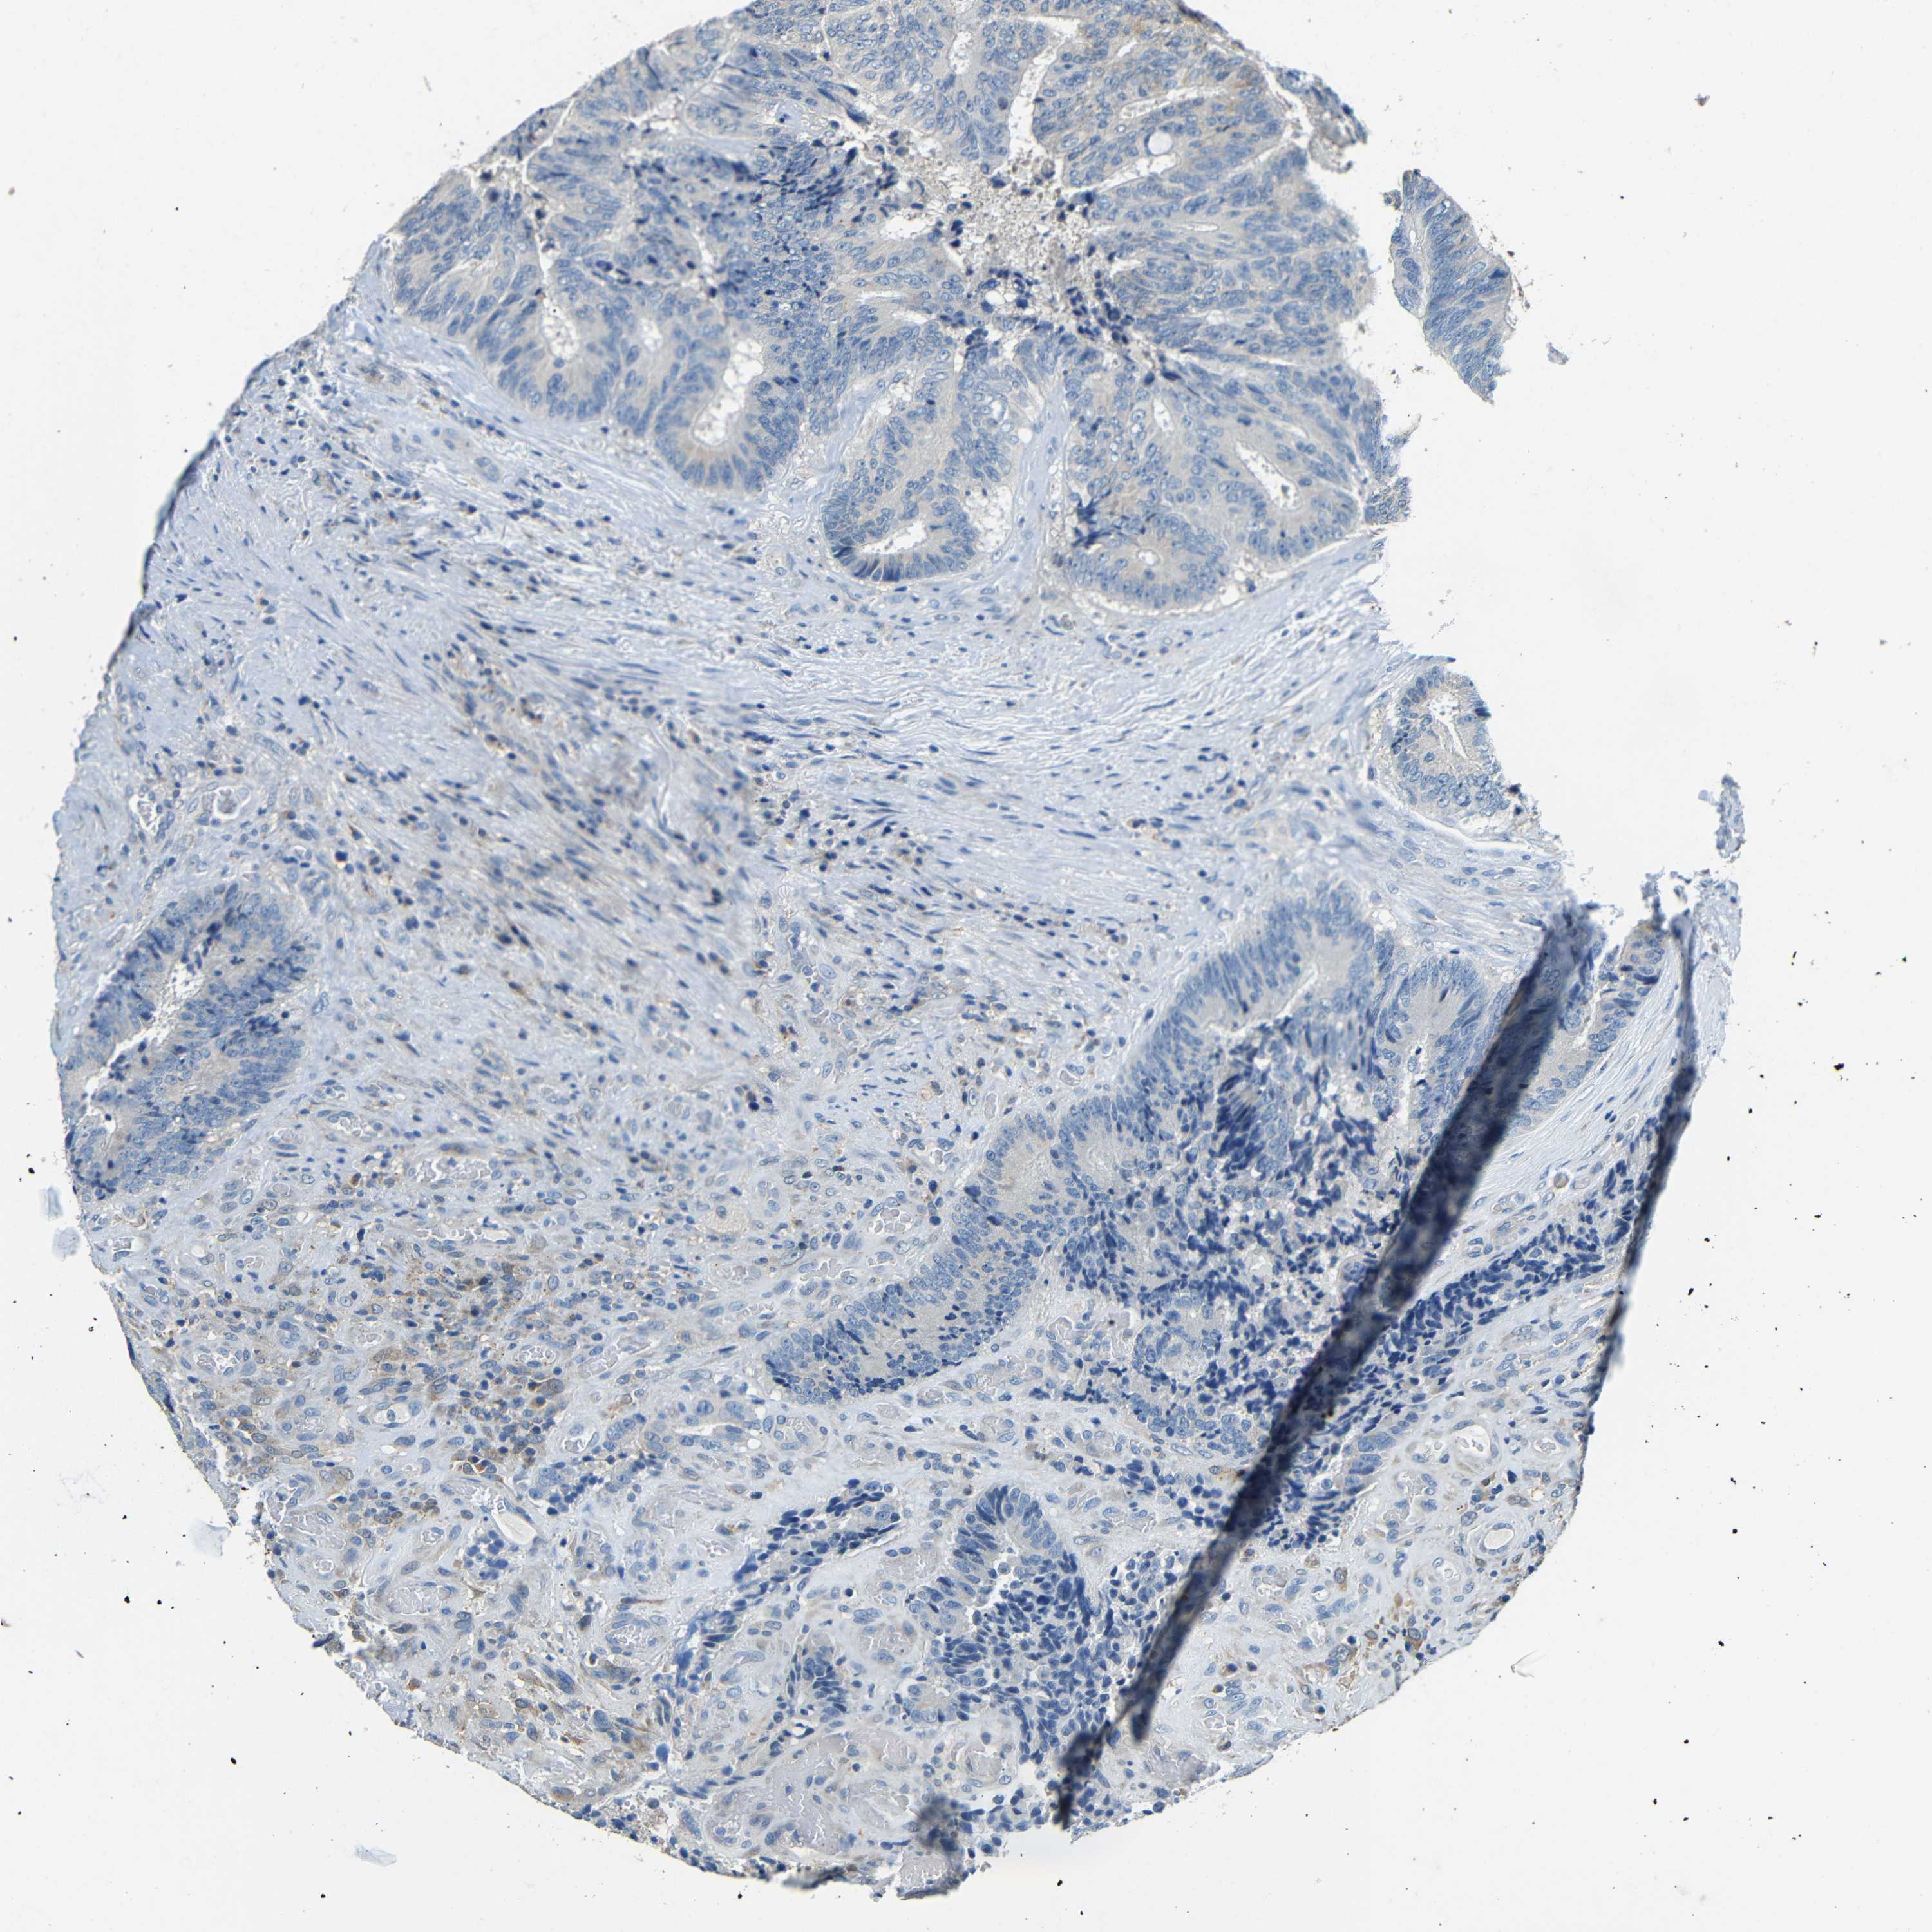

COLON ADENOCARCINOMA (VALIDATION) - Interactive survival scatter ploti

The Survival Scatter plot shows the clinical status (i.e. dead or alive) for all individuals in the patient cohort, based on the same data that underlies the corresponding Kaplan-Meier plots. Patients that are alive at last time for follow-up are shown in blue and patients who have died during the study are shown in red.

The x-axis shows the expression levels (FPKM) of the investigated gene in the tumor tissue at the time of diagnosis. The y-axis shows the follow-up time after diagnosis (years). Both axes are complimented with kernel density curves demonstrating the data density over the axes. The top density plot shows the expression levels (FPKM) distribution among dead (red) and alive patients (blue). The right density plot shows the data density of the survived years of dead patients with high and low expression levels respectively, stratified using the cutoff indicated by the vertical dashed line through the Survival Scatter plot. This cutoff is automatically defined based on the FPKM cutoff that minimizes the p-score. The cutoff can be changed by dragging the vertical line or by entering a cutoff value in the square labeled "Current cut-off".

Under the Survival Scatter plot the p-score landscape (black curve; left axis) is shown together with dead median separation (red curve; right axis). Dead median separation is the difference in median mRNA expression between patients who have died with high and low expression, respectively. It is calculated as follows: median FPKM expression of dead patients with high expression - median FPKM expression of dead patients with low expression. This is intended to aid the user in visually exploring custom cutoffs and the associated p-scores and dead median separation.

Individual patient data is displayed and can be filtered by clicking on one or more of the category buttons on the top of the page. Categories describing expression level and patient information include: high, low, alive, dead, female, male and tumor stages. The scale of the x-axis can be toggled between linear and log-scale by clicking on the "x log" button. Mouse-over function shows TCGA ID, patient information and mRNA expression (FPKM) for each patient.

& Survival analysisi

Kaplan-Meier plots summarize results from analysis of correlation between mRNA expression level and patient survival. Patients were divided based on level of expression into one of the two groups "low" (under cut off) or "high" (over cut off). X-axis shows time for survival (years) and y-axis shows the probability of survival, where 1.0 corresponds to 100 percent.

FMO5 is not prognostic in Colon Adenocarcinoma (validation)

Best expression cut offi

Based on the FPKM value of each gene, patients were classified into two groups and association between prognosis (survival) and gene expression (FPKM) was examined. The best expression cut-off refers the FPKM value that yields maximal difference with regard to survival between the two groups at the lowest log-rank P-value. Best expression cut-off was selected based on survival analysis .

When clicking on this number, the vertical dashed line indicating cut-off, the interactive survival plot, and the Kaplan-Meier curve will be adjusted to show results based on the best expression cut-off.

: 10.76

Median expressioni

Median expression refers to the median FPKM value calculated based on the gene expression (FPKM) data from all patients in this dataset. When clicking on this number, the vertical dashed line indicating cut-off, the interactive survival plot, and the Kaplan-Meier curve will be adjusted to show results based on the median expression.

: N/A

P scorei

Log-rank P value for Kaplan-Meier plot showing results from analysis of correlation between mRNA expression level and patient survival.

N/A

5-year survival highi

5-year survival for patients with higher expression than the expression cutoff.

For melanoma and glioma, 3-year survival is shown.

5-year survival lowi

5-year survival for patients with lower expression than the expression cutoff.

Average pTPM 17.3

Number of samples 486